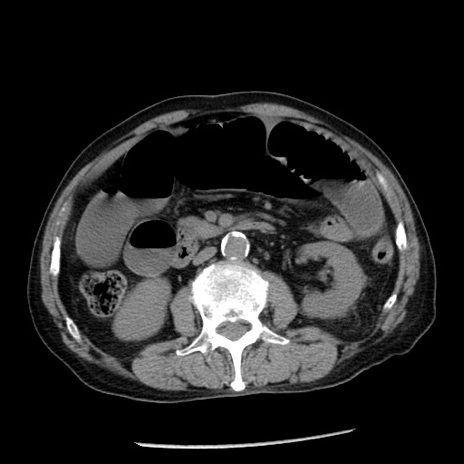

症例26(横断像)

【症例】80歳代男性

【主訴】嘔吐

【現病歴】昨晩2回嘔吐あり、今朝になっても嘔吐あり。来院。

【既往歴】胃潰瘍

【身体所見】意識清明、BT 37.6℃、BP 166/95mmHg、HR 100bpm、SpO2 97%、腹部:平坦・軟、腸蠕動音聴取良好、圧痛なし。

【データ】WBC 21900、CRP 1.46